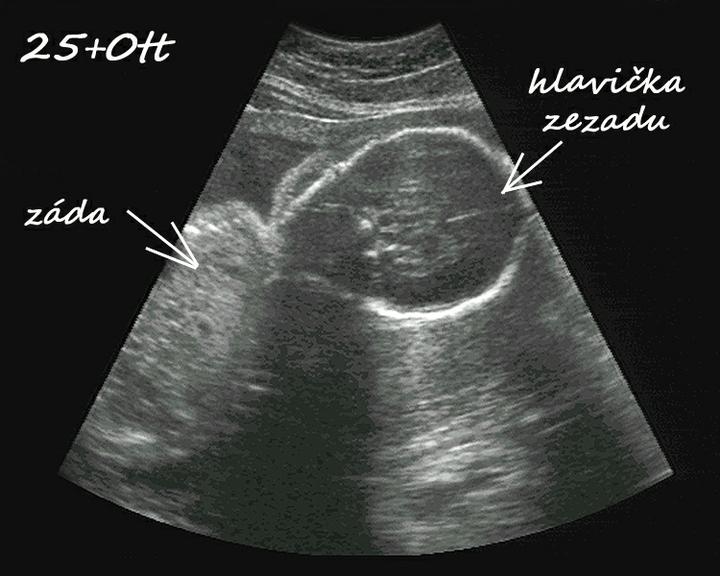

začínám 30tt-24.7. ultrazvuk, malá je snad zdravoučká a už ted je to naše láska 🙂 má odhadem v 29+0tt 1357g, rozměry bříška a hlavičky odpovídají stáří, ale nožička je o týden delší. No prý to bude dlouhán, což mě pobavilo, protože Nikolka měla při narození jen 43cm ( 36+3tt ). Tak uvidíme, jestli budou sestřičky každá úplně jiná 🙂